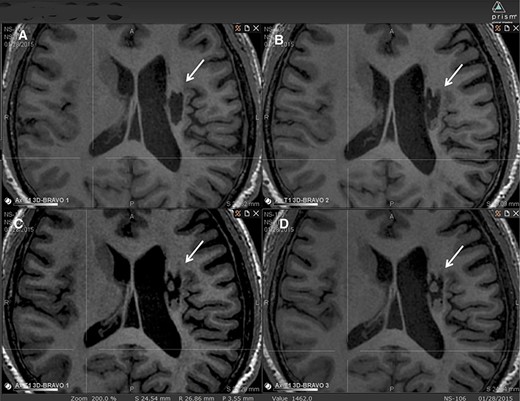

圖2:腔內組織生長(cháng)的縱向MRI示例。

圖中顯示了B組 (#106) 受試者在T1MRI上隨時(shí)間的變化。

(A):基線(xiàn)時(shí),(B) 6個(gè)月隨訪(fǎng)時(shí),(C) 12個(gè)月隨訪(fǎng)時(shí),(D) 24個(gè)月隨訪(fǎng)時(shí)。箭頭表示梗塞腔。

可以看到兩個(gè)組織團塊,在基線(xiàn)時(shí)不存在,推測是來(lái)自植入的NSI-566,隨著(zhù)時(shí)間的推移,它們似乎慢慢填滿(mǎn)了腔體。